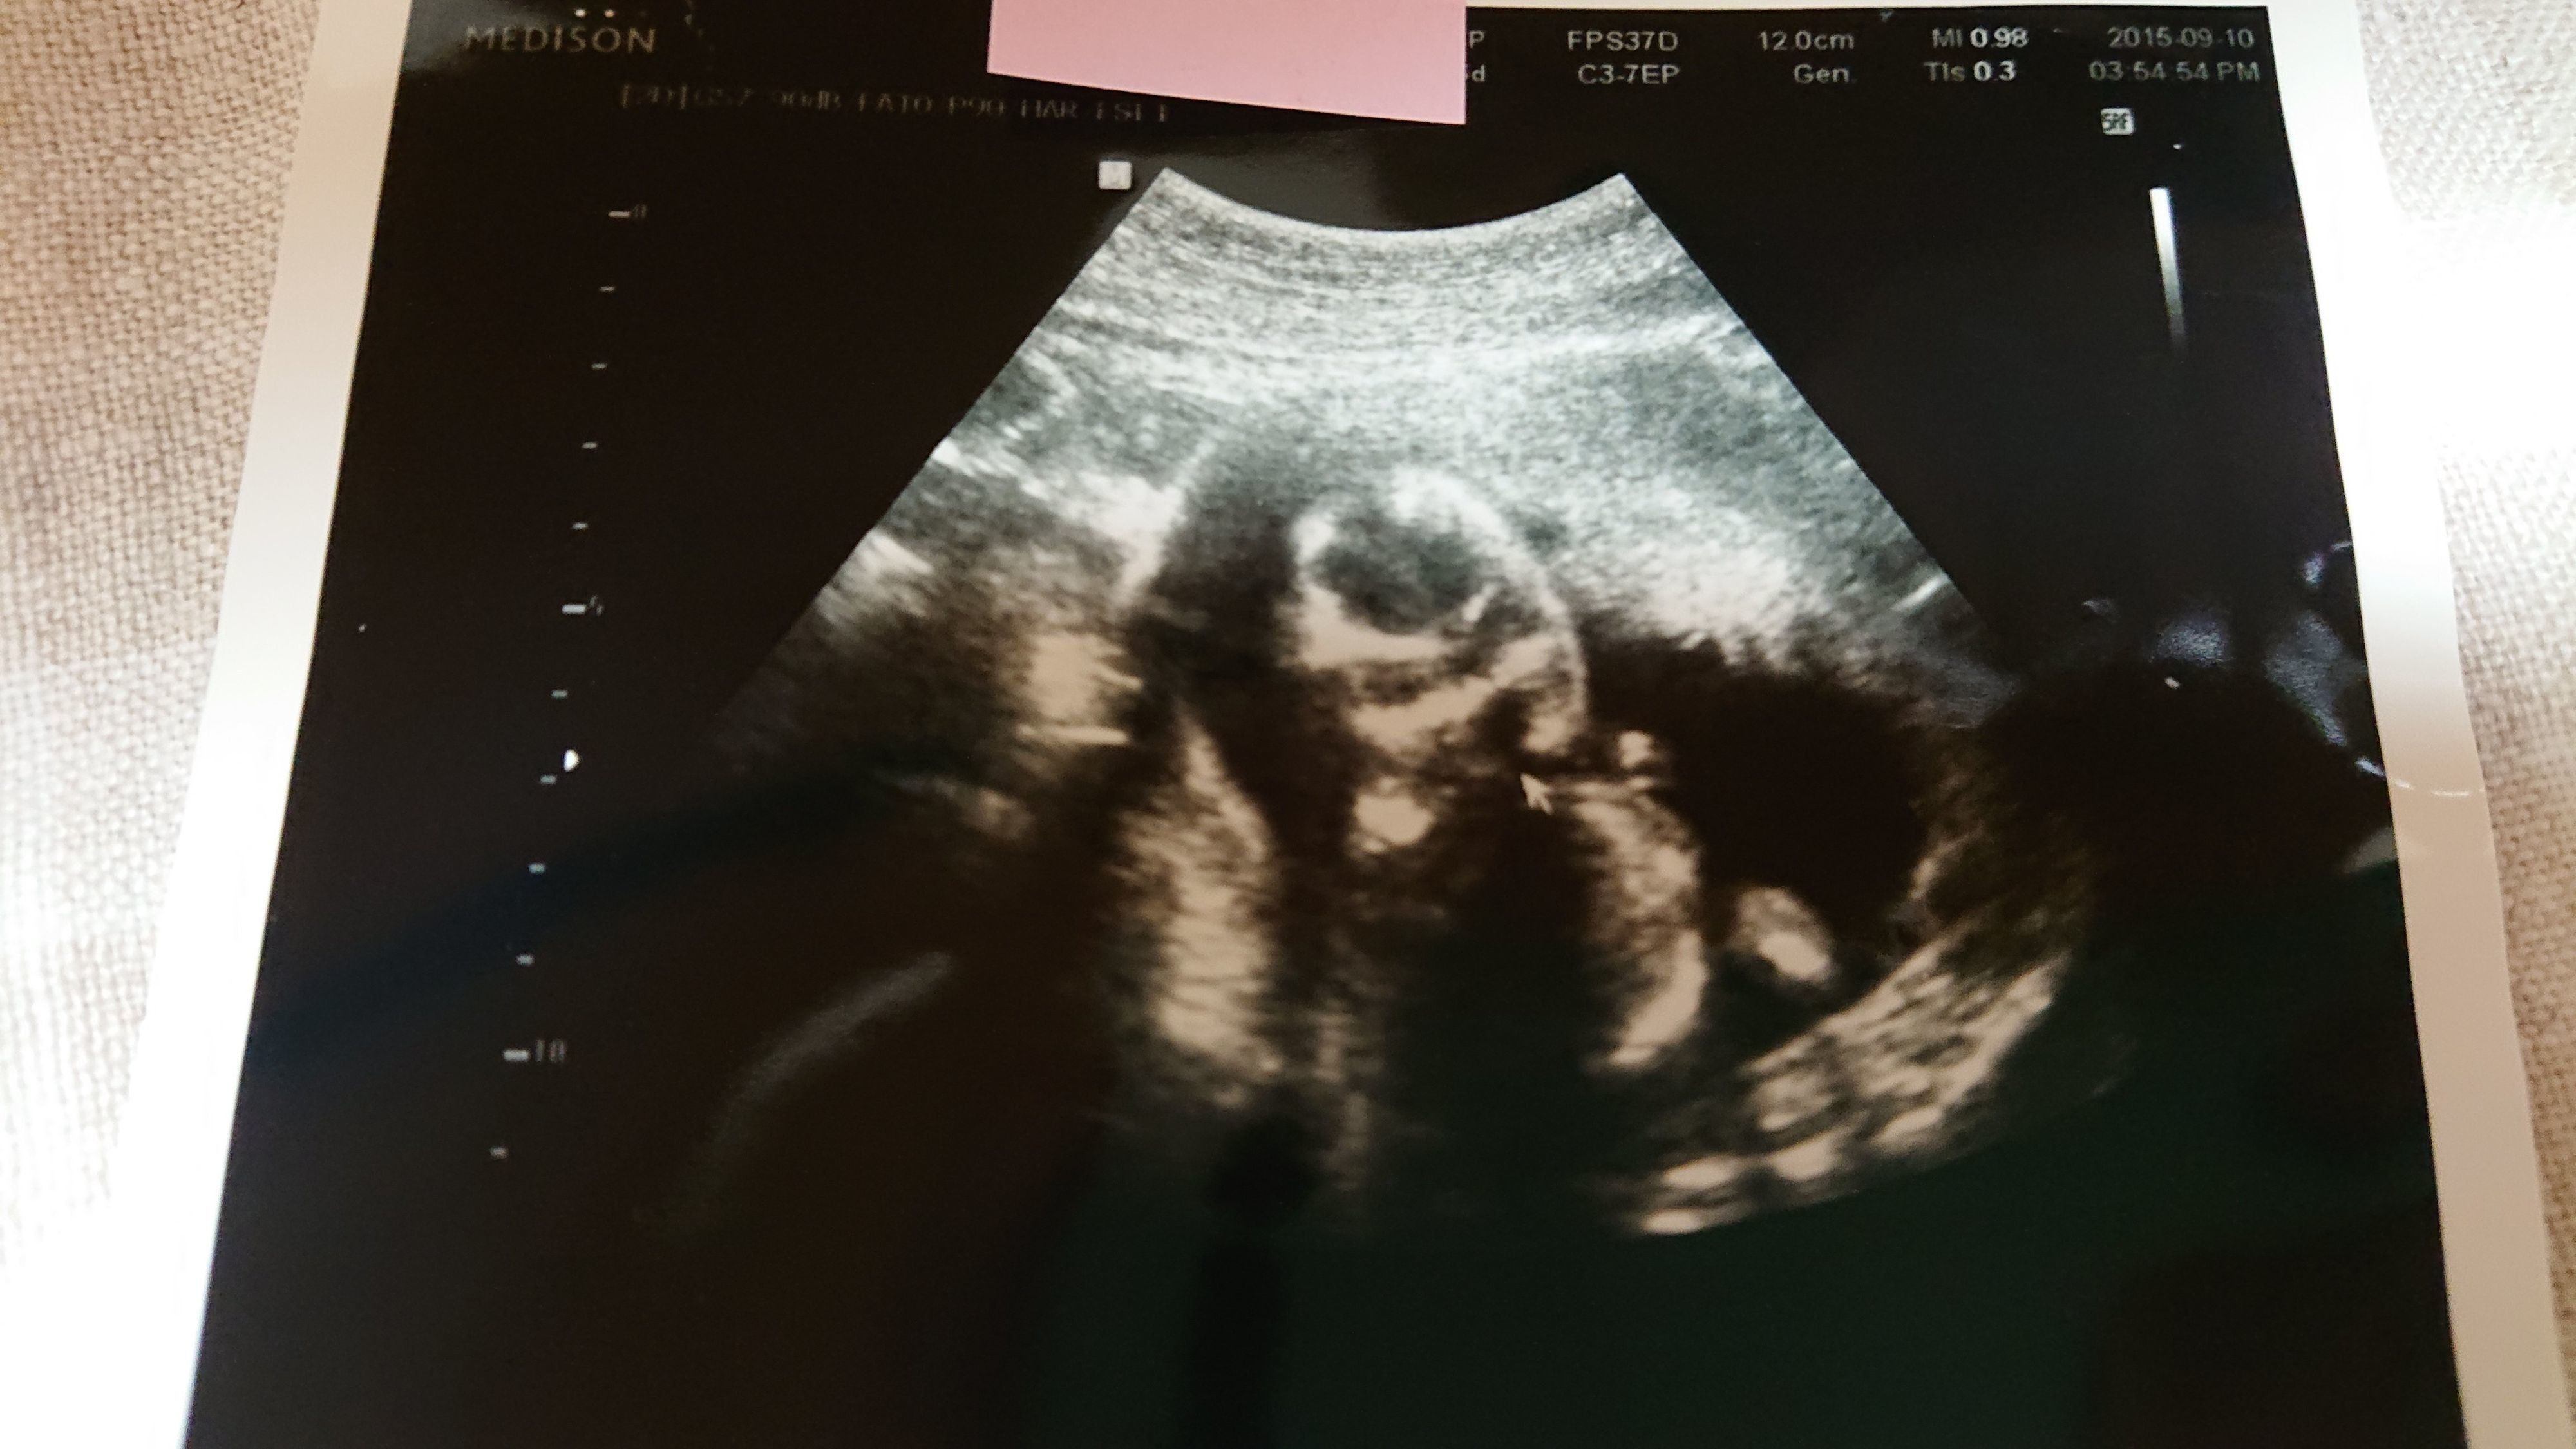

《妊娠30週目のエコー写真》

この写真を撮る2週間程前に切迫早産で入院してしまったのですが、入院してから初めて撮った30週目のエコー写真です。妊娠後期になってくると、赤ちゃんが大きくなりすぎて、ほんの一部しかエコー写真に写らなくなってきました。「赤ちゃんの顔が見たい」と思っても、この日は赤ちゃんの向きが合わずに見ることができませんでした。「赤ちゃんの向きによって、赤ちゃんの顔を見られずに終わってしまう時もある」と、医師に言われて、何だか残念に思ったものです。